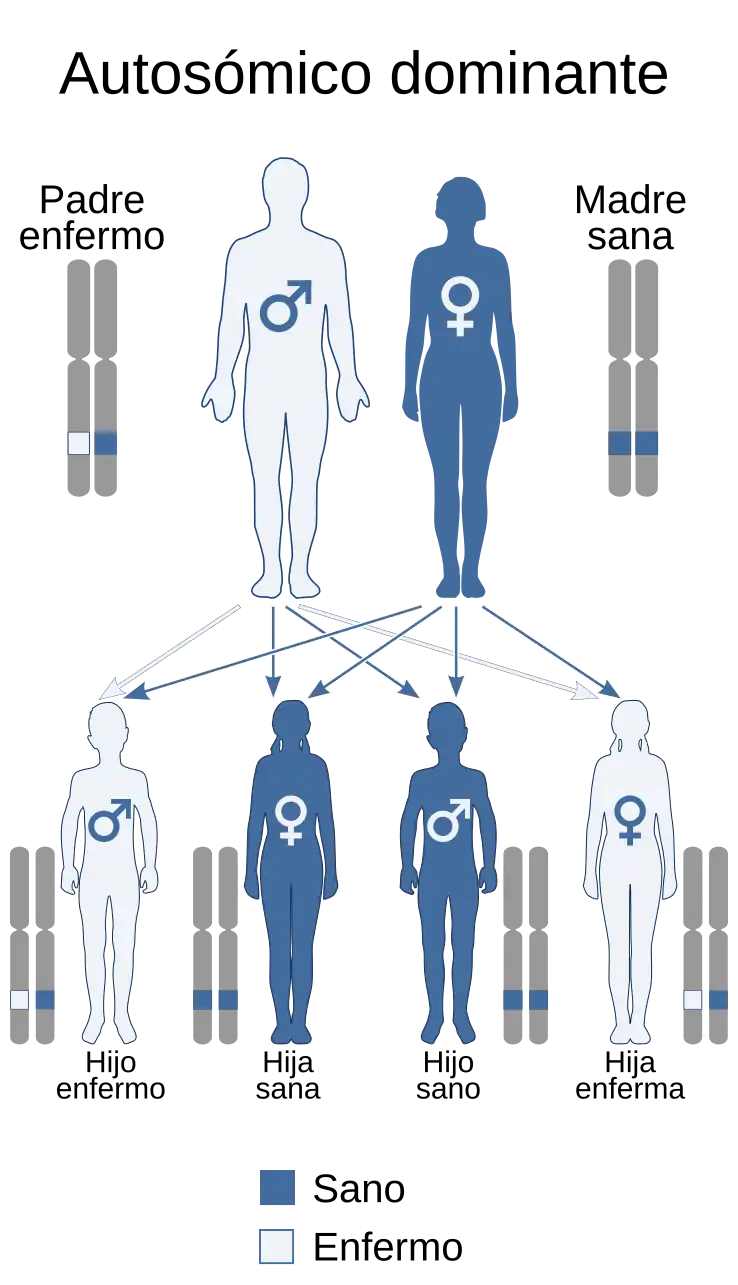

La enfermedad de von Hippel-Lindau (VHL, también conocida por sus sinónimos angiomatosis familiar cerebeloretinal, hemangioblastomatosis o angiofacomatosis retiniana y cerebelosa), consiste en la aparición de múltiples tumores en diferentes órganos a lo largo de toda la vida del individuo. Se cataloga como una enfermedad rara de carácter hereditario autosómico dominante.

La enfermedad se manifiesta mediante un patrón autosómico dominante. Está relacionada con una mutación genética en la síntesis del gen supresor tumoral de von Hippel-Lindau (VHL), situado en el cromosoma 3. Según establece la hipótesis de Knudson, para que se exprese el fenotipo, es necesario que el individuo sea previamente portador de la mutación en uno de los alelos, y posteriormente la mutación somática del segundo. A este mecanismo se le conoce como pérdida de heterocigosidad (abreviado como LOH, por sus siglas en inglés: loss of heterozygosity).[5] En la mayoría de los afectados por el síndrome (80%), la mutación constitutiva del gen VHL es heredada del progenitor, y la mutación de novo es la responsable del 20% de los casos de la enfermedad de von Hippel-Lindau. Se han descrito casos de mosaicismo parecental, pero su incidencia no es conocida. La descendencia de un individuo con VHL posee una riesgo del 50% de heredar la mutación causante de la enfermedad. Las pruebas prenatales en los embarazos en riesgo es posible si la mutación causante de la enfermedad ha sido identificada previamente en un miembro de la familia.[6] Muy raramente, la mutación se origina en la etapa embrionaria. En ese momento la presencia del gen es solo parcial en el embrión aún no formado (mosaicismo).[7] Se ha probado que el polimorfismo en el gen de la ciclina D1 (CCND1) en el locus 11q13 puede verse modificado en fenotipos afectados por la mutación del gen VHL.[8]

La causa de la enfermedad es una mutación que afecta al gen oncosupresor VHL, el cual se encuentra en el brazo corto del cromosoma 3. Existe una amplia variedad en cuanto a la edad de inicio de la enfermedad, el órgano afectado y la gravedad del efecto. La mayor parte de los afectados del síndrome de von Hippel-Lindau heredan una copia alterada del gen, de uno de los progenitores. No obstante, en aproximadamente un 20% de los casos el gen alterado es el resultado de una nueva mutación que se da durante la formación de las células germinales o en el desarrollo embrionario.